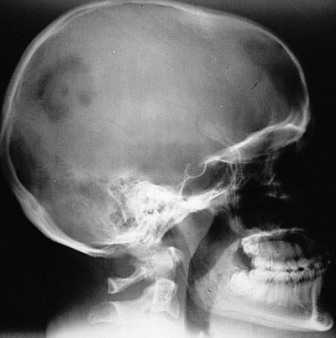

При гистиоцитозе таких пневмотораксов случается много. Это часто помогает поставить правильный диагноз. Из костей у взрослого человека при гистиоцитозе страдают преимущественно кости черепа, таза и ребра. В них появляются очаги разрушения, и как следствие возникают «патологические» переломы.

Затем для подтверждения диагноза проводят видеоторакоскопическую биопсию легкого. При данном диагнозе простое проведение бронхофиброскопии с биопсией даст очень мало информации. Чтобы определить степень поражения других органов при гистиоцитозе проводят: рентгенографию скелета и черепа, по показаниям (при подозрении на поражение головного мозга) - магнитнорезонансную томографию (МРТ).

Чтобы установить диагноз «гистиоцитоз из клеток Лангерганса», нужно взять фрагмент легкого на гистологический и иммуногистохимический анализ. Если диагноз подтвердился, то всех пациентов ради исключения системного процесса необходимо обследовать для оценки сохранности костной ткани (рентгенография черепа, костей грудной клетки и таза) и исключить изменения в других органах (печень, кожа…), если есть жалобы.